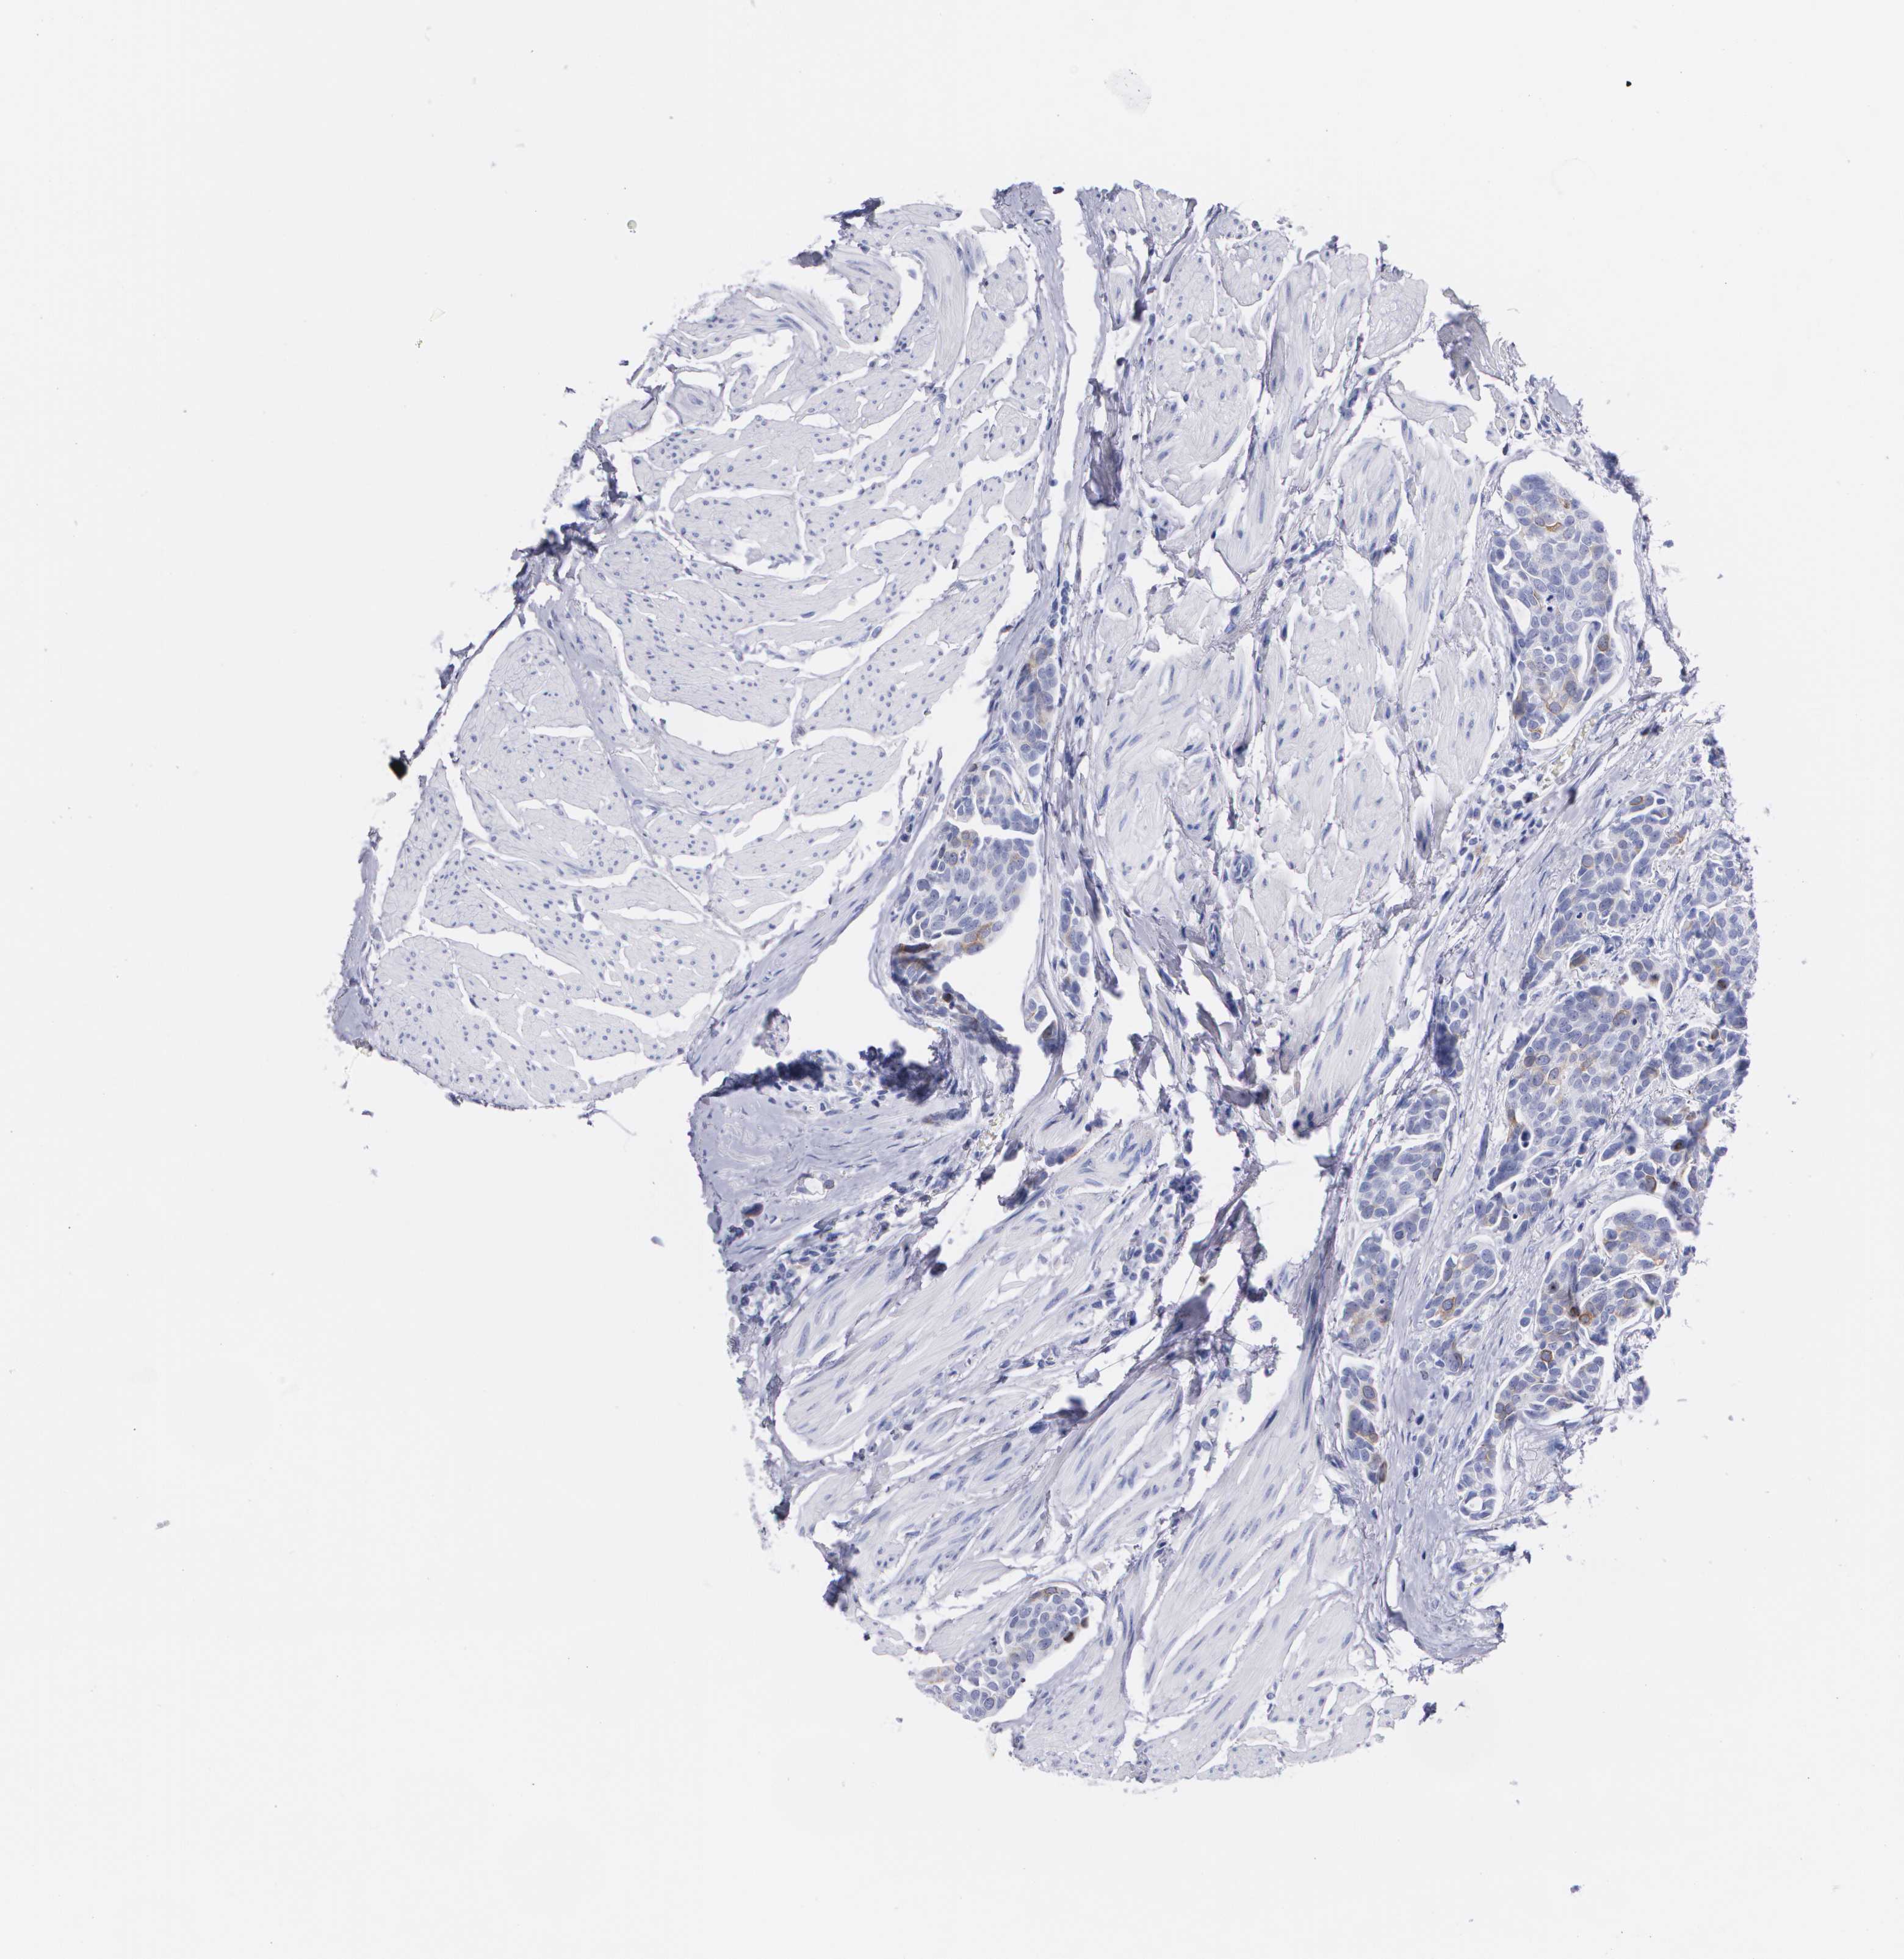

UROTHELIAL CANCER - Protein expressioni

A mouse-over function shows sample information and annotation data. Click on an image to view it in a full screen mode. Samples can be filtered based on level of antibody staining by selecting one or several of the following categories: high, medium, low and not detected. The assay and annotation is described here.

Antibody stainingi

Antibody staining in the annotated cell types in the current human tissue is reported as not detected, low, medium, or high, based on conventional immunohistochemistry profiling in selected tissues. This score is based on the combination of the staining intensity and fraction of stained cells.

Each image is clickable and will lead to virtual microscopy that enables deeper exploration of all samples and also displays staining intensity scores, fraction scores and subcellular localization as well as patient and tissue information for each sample.

Antibody HPA040025

Antibody CAB002433

Urothelial carcinoma, High grade

Urothelial carcinoma, NOS

Urothelial carcinoma, Low grade